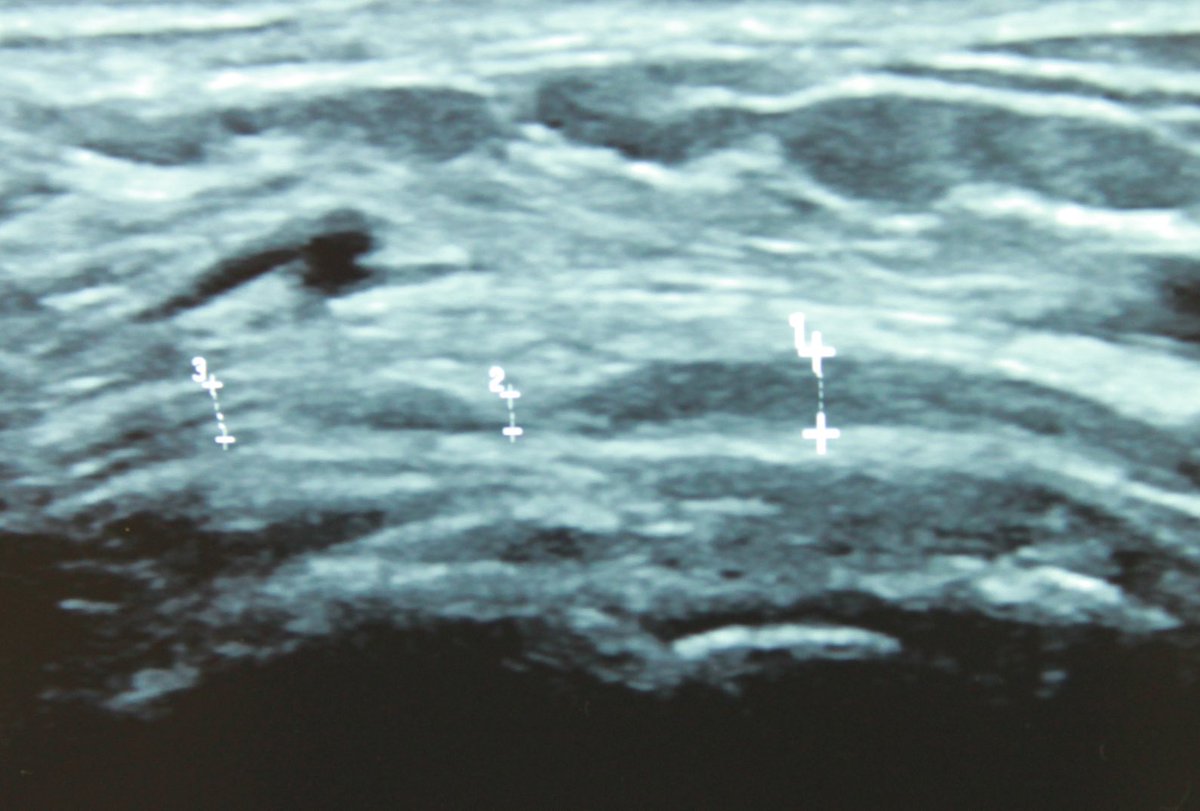

#HEELPAIN can be produced by the MEDIAL CALCANEAL NERVE. My patient’s pain was reproduced by palpation exactly where it was compressed. See site 2 - diameter is reduced with an hour-glass deformity (US). #neurodynamics #physiotherapy #physicaltherapy #chiropractic

Neurodynamics's tweet image. #HEELPAIN can be produced by the MEDIAL CALCANEAL NERVE.

My patient’s pain was reproduced by palpation exactly where it was compressed.

See site 2 - diameter is reduced with an hour-glass deformity (US).